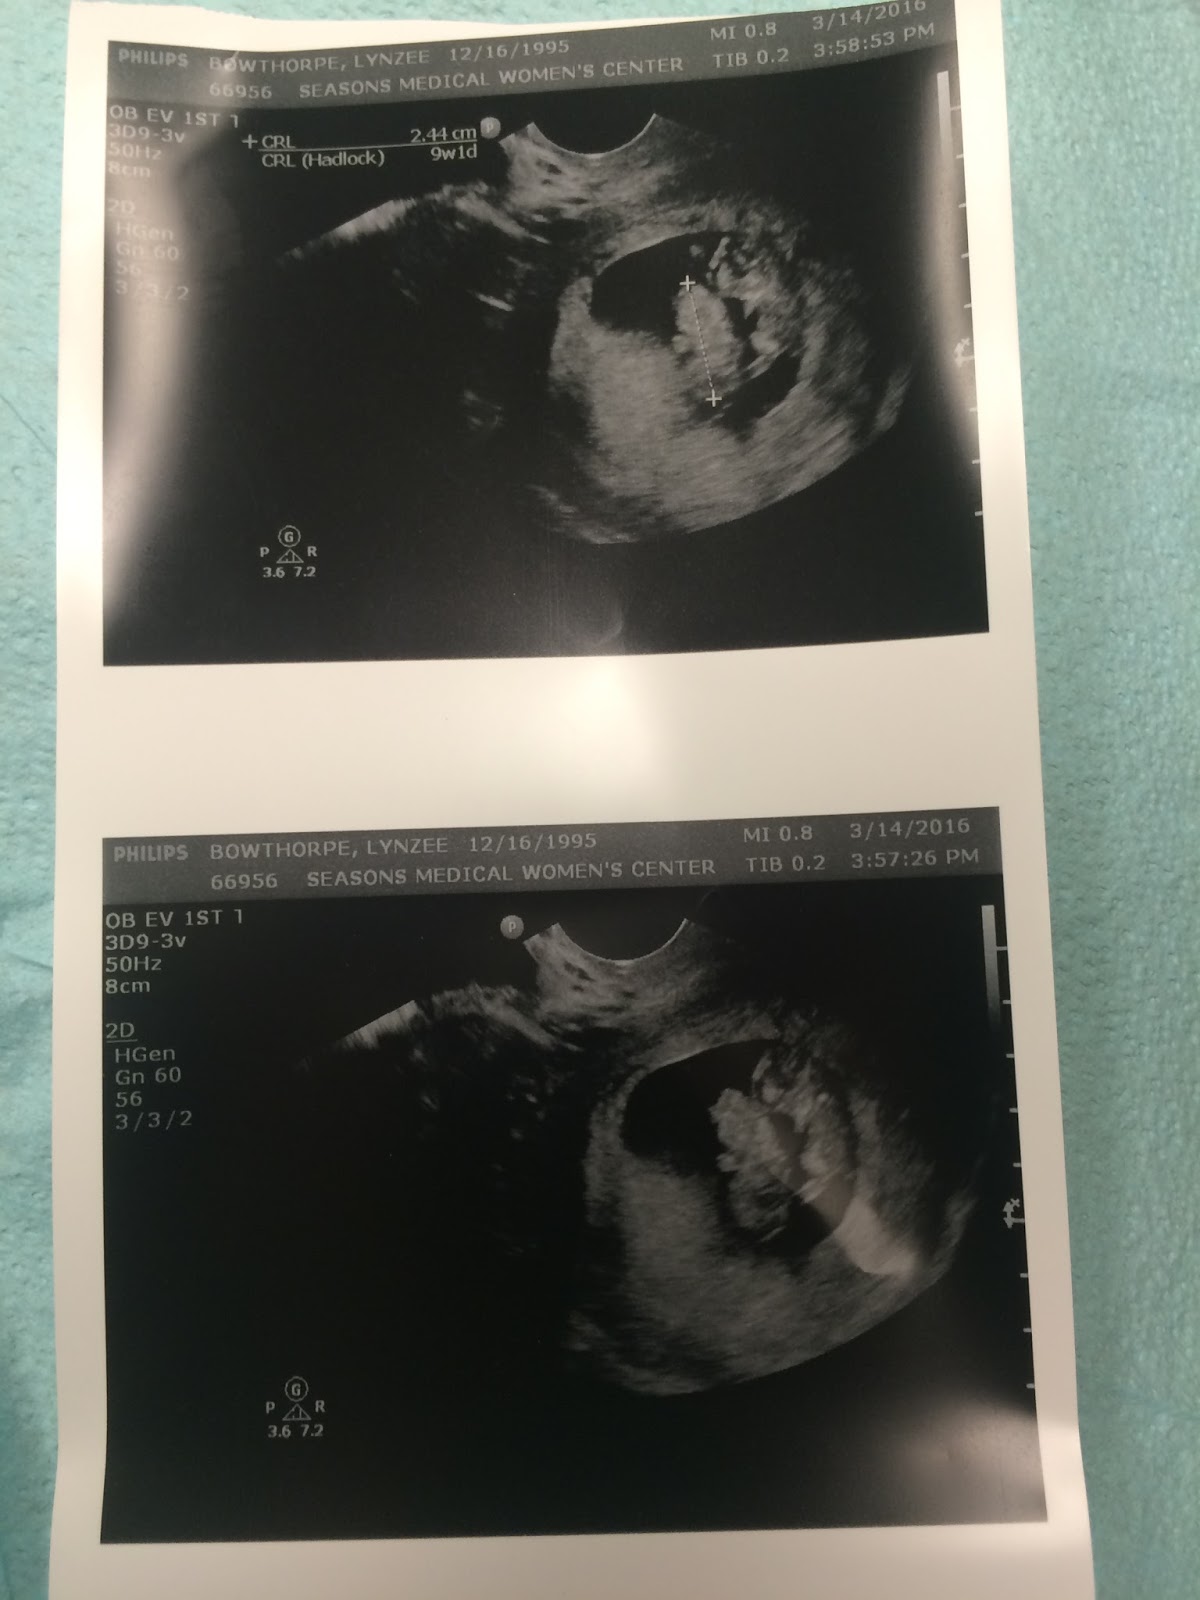

“Just a few days ago (well 14 days now,) Warren and I got a big surprise. Two weeks ago, Monday, at my first ultrasound, the 14th of March, we learned that we are expecting twins. Two little figures showed white against the darkness, and two little heartbeats were heard. Warren was the first to detect the presence of more than one, and was afraid to speak out for fear he was right. When he did ask the midwife, “Only one?” she moved around and realized there were two of them! We had to wait in the ultrasound room for an hour then until an ultrasound tech specialist could come measure their progress and give me an updated EDD. When she finally came, we learned the younger of the two was 9weeks and 3 days at the time, and their due date was subject to a few weeks fluctuation. We also learned the type of twins we are expecting and that I would be coming in much more frequently than I’d previously expected to, the first of which being only one week from that day!”

“I had another ultrasound, just one week after that first one. We needed to go in and meet with an OB (since originally I had met with a midwife as that was my preference.) We got lots more pictures of my little ones to look at while we wait for the next visit, (which I will be getting an ultrasound visit every two weeks as my pregnancy is a more ” high-risk”) The news is now almost constantly on the brain, “Twins. I am making twins. There are going to be two babies…” But being sore and nauseous is pretty annoying at this point, so I am counting the days until the glorious SECOND TRIMESTER when they say this can be over!”